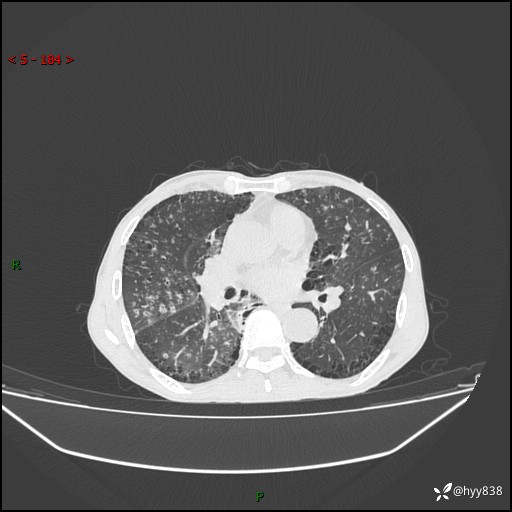

胸部CT平扫